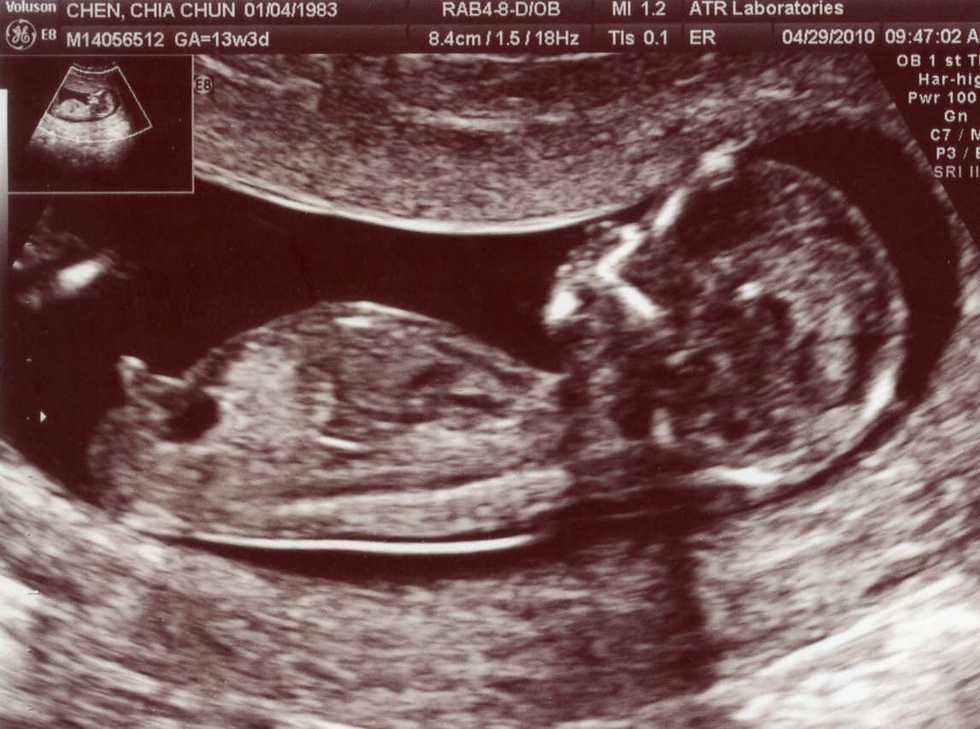

Now I will move on to the second factor that comes into play when wanting to abort your child. Most times when you are pregnant everything usually goes okay but there are times when things can go wrong. There are times when you know your child is going to have a lot of health issues and a low chance of survival once it leaves the womb, sometimes it may even be so bad that the baby won't even make it till birth and you may end up having to give a still birth. What if you found out that the baby would have no skull, one arm, no legs and the heart was outside of the body and this child would have no chance of survival outside the womb. I know someone personally who had this issue so it can happen and it's not something I just came up with off the top of my head. This person wanted to carry the baby to full term because it was doing okay and she did not want to get an abortion because she was afraid of people calling her a whore, a murderer, a bad person. Now it has gotten to the point that since the baby's organs are outside of the body that they can become septic, meaning poisonous. This could cause her health issues, so, she has no choice but to abort because she has a family and a son that need her. The heart was at a good rate but now it is slowing and the baby may not even be alive by the time she goes to get an abortion.